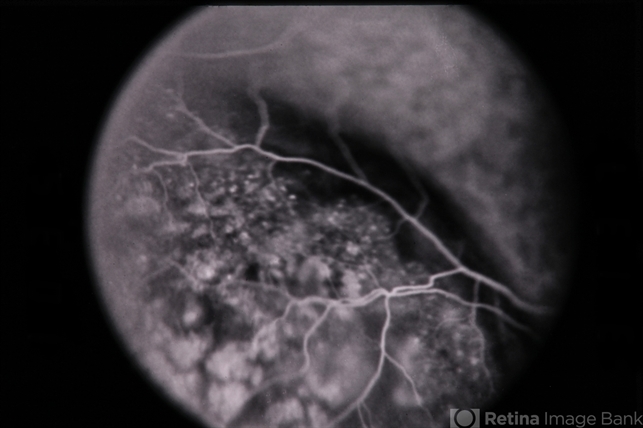

Choroidal Melanoma

Choroidal melanoma.